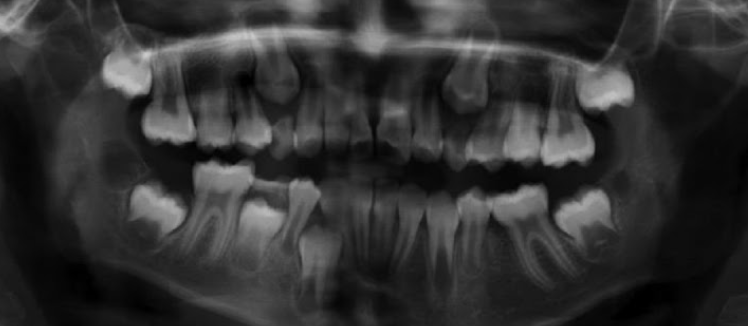

1.Lower adult CI there? YES. so def 6-7

1. Upper adult CI there (they normally erupt 7-8)? NO, baby ones should shed at 6-7.

Conc: pt. Is 6 y.o